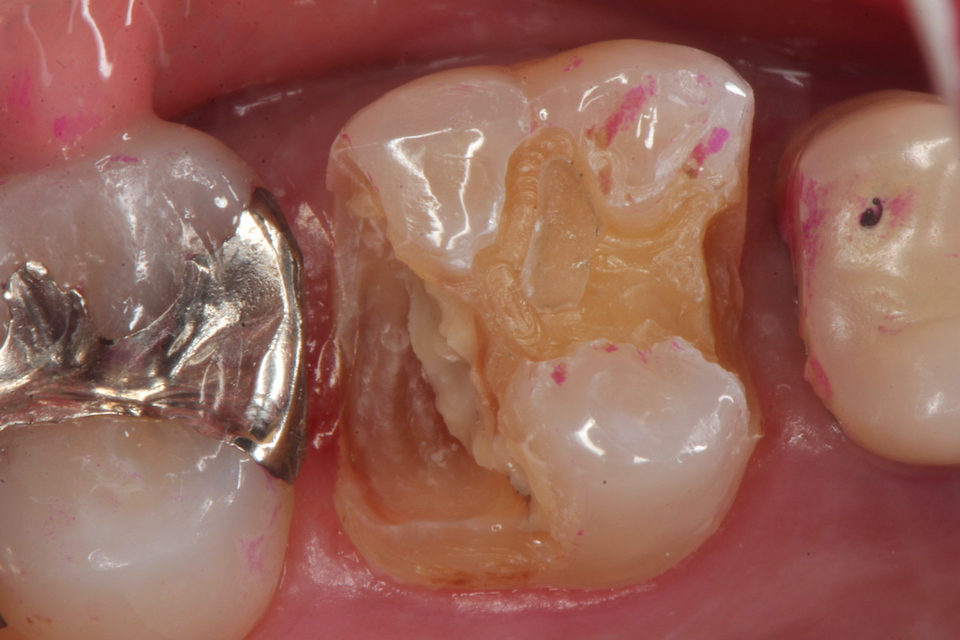

ブリッジ脱離で2次カリエス+Perでグラグ… 2025.11.01

ブリッジ脱離で2次カリエス+Perでグラグ… 2025.10.31